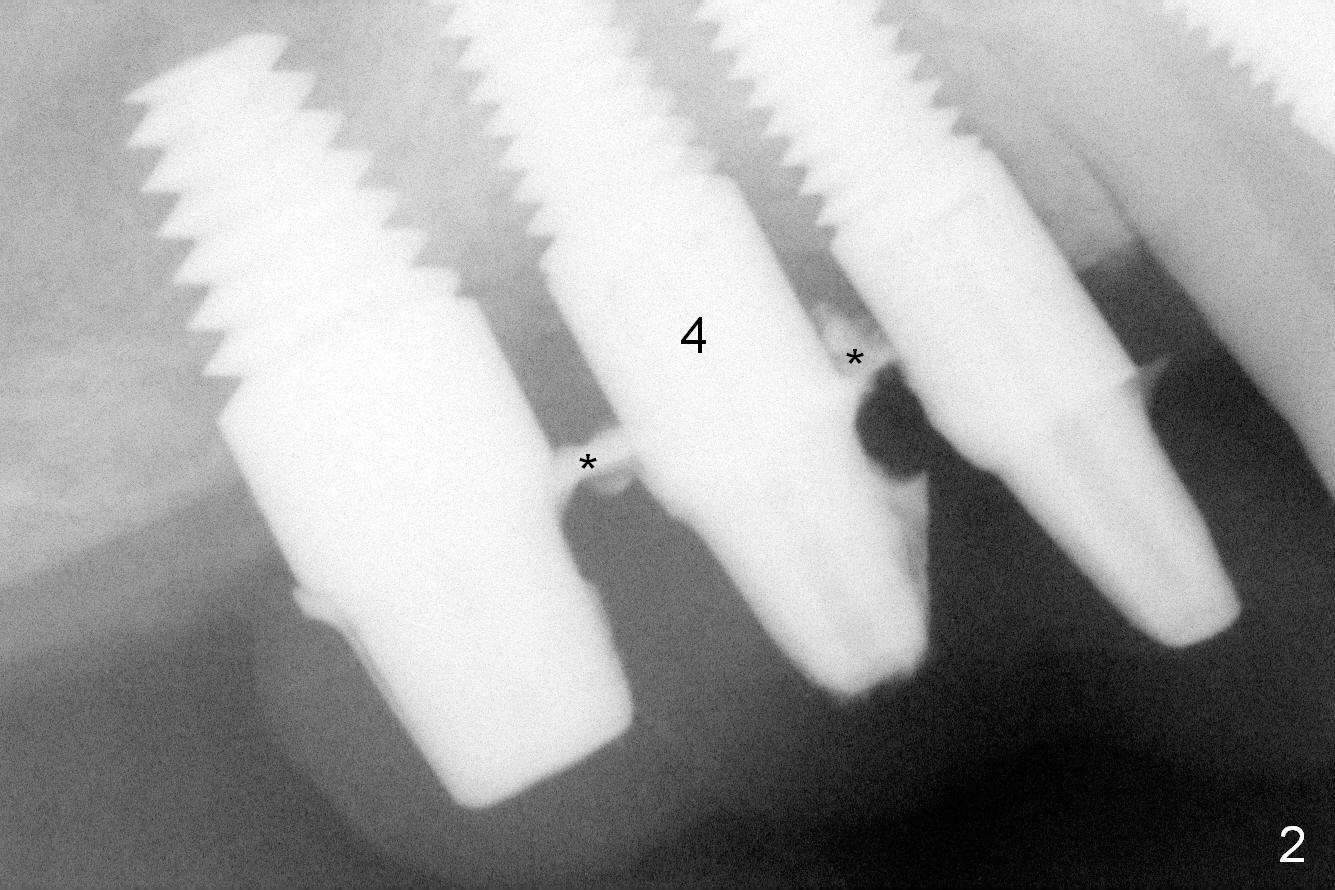

After reconfirmation of the deepest pocket between the implants at #3 and 4, a palatal sulcus incision is made with reflection of the flap. After granulation tissue curettage, a crater is found palatal to the implant at #4 (Fig.1 arrowheads), consistent with preop CT coronal section (Fig.3 *). Another complicating factor is excess temporary cement used for splinted provisional between #3 and 5 (Fig.2 *) between 0.5 and 4 months post #4 implant placement.